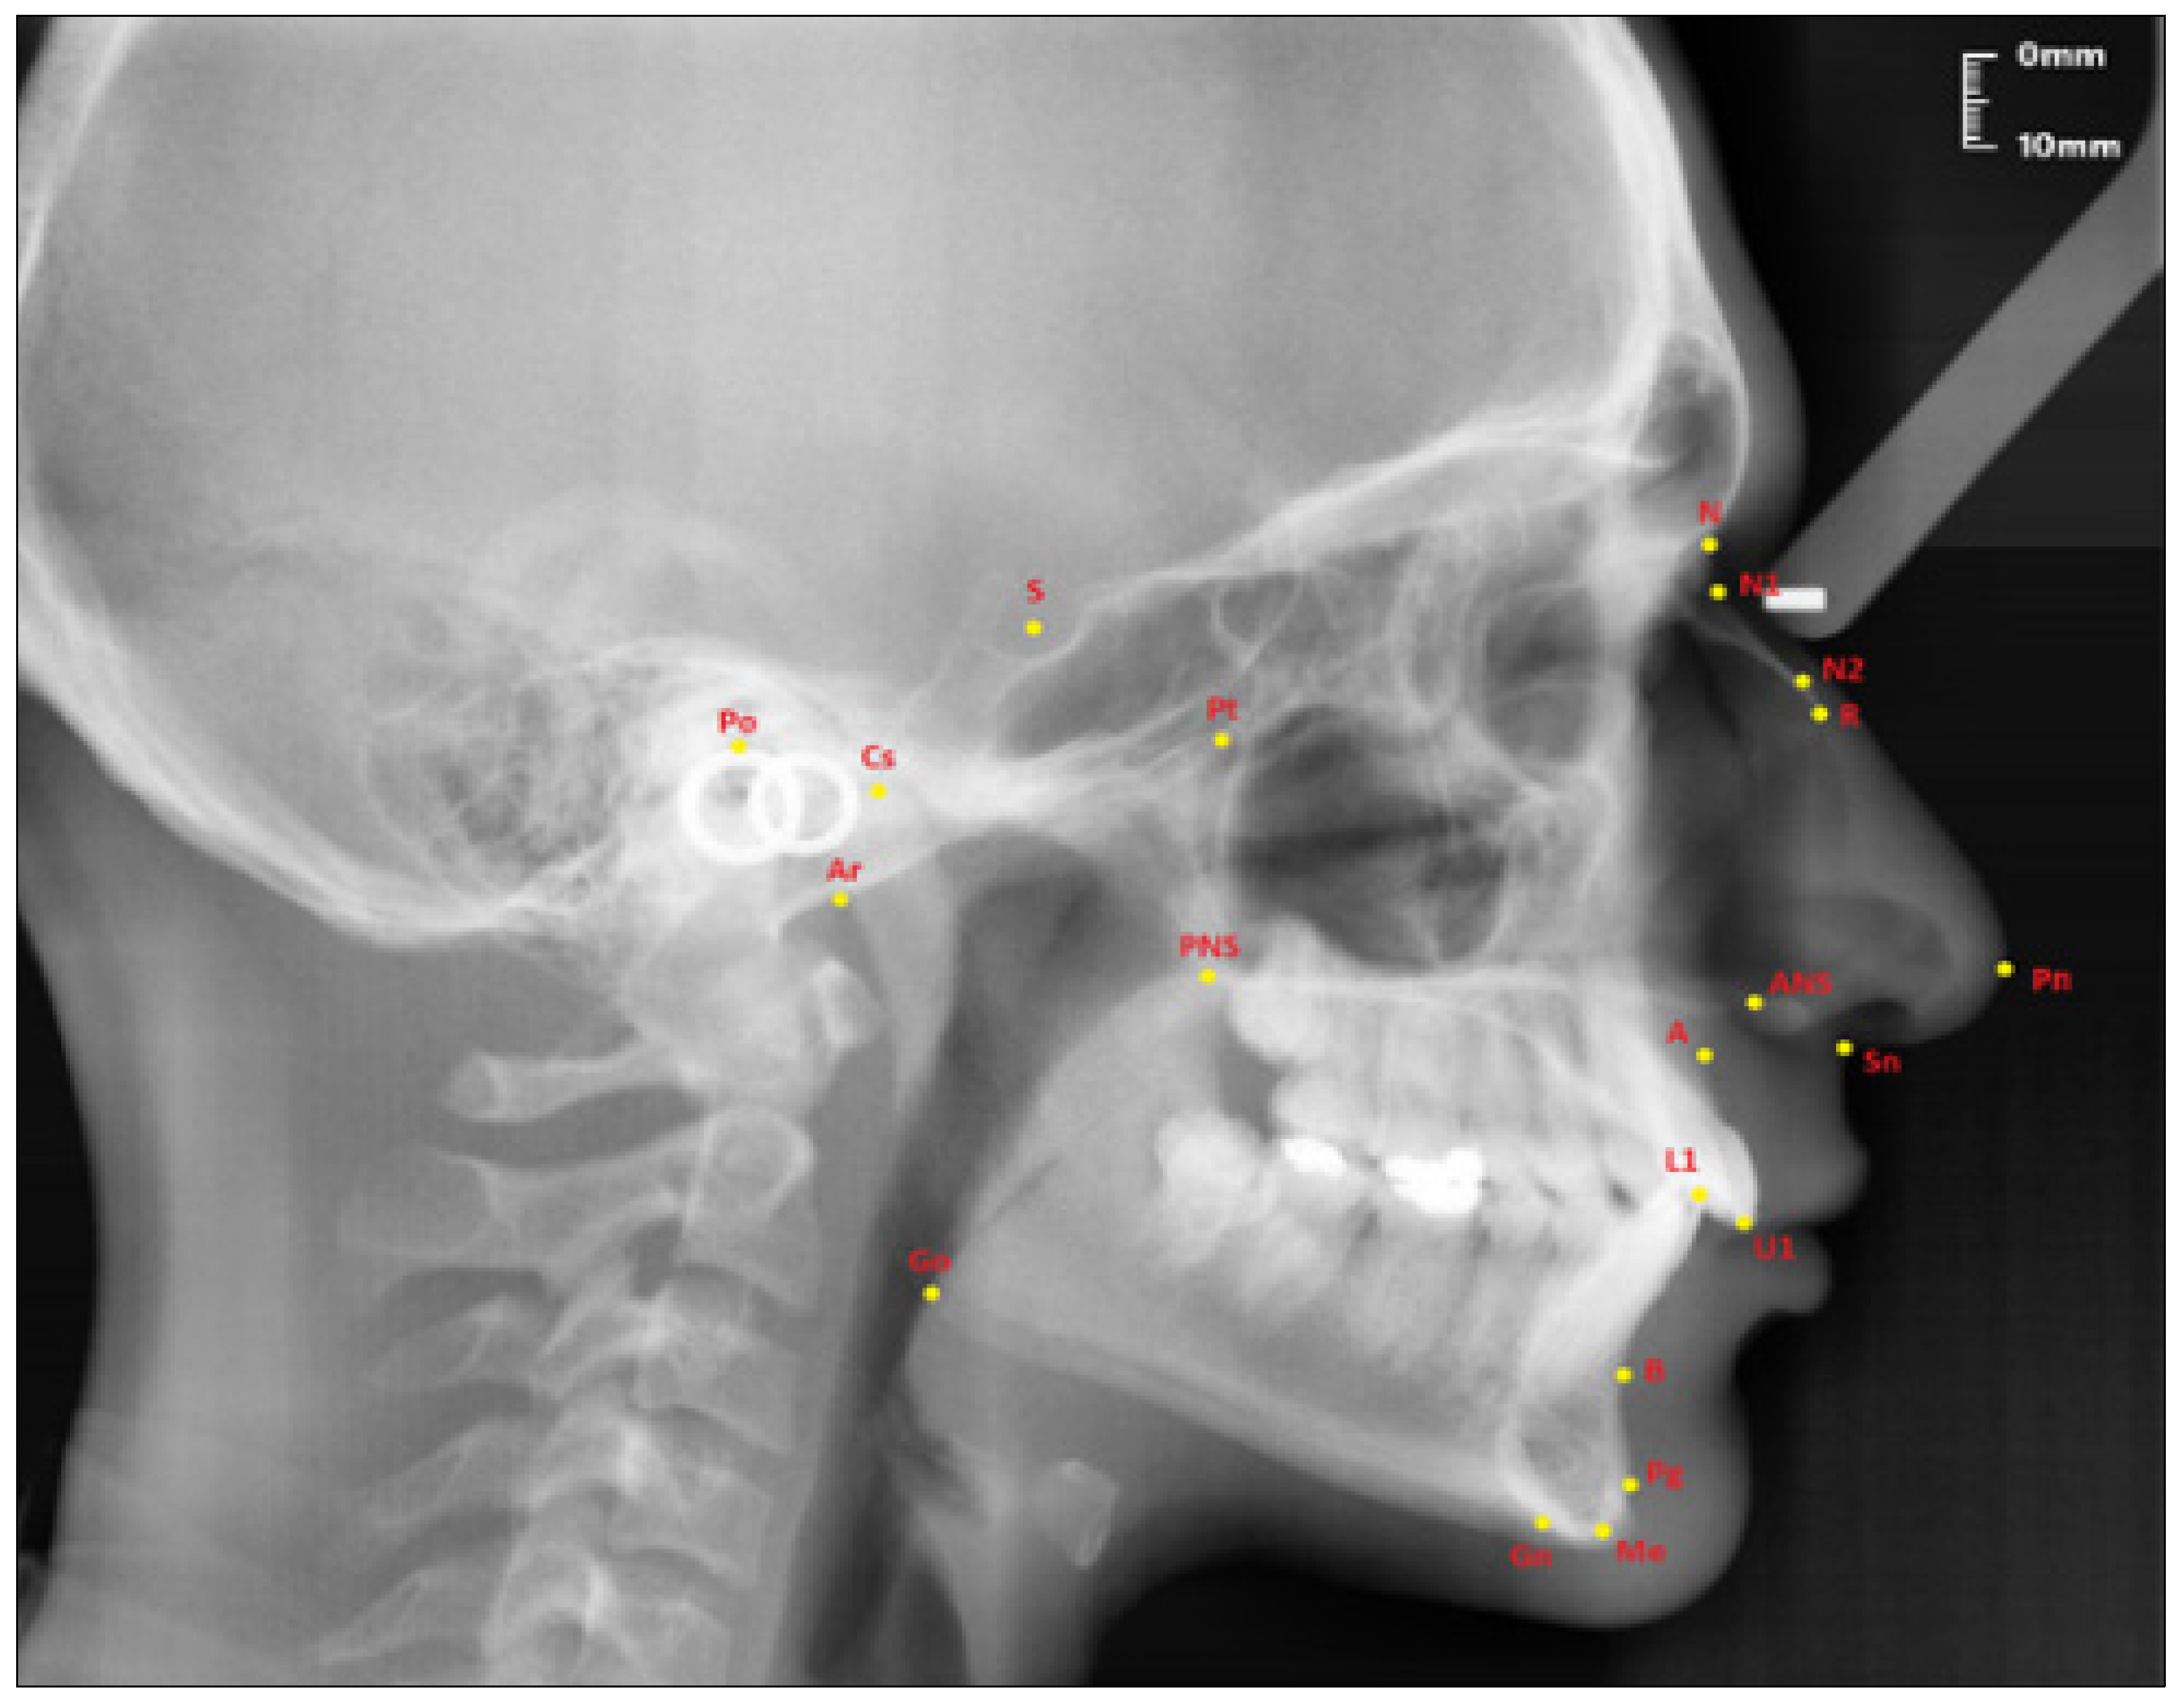

The points used in lateral cephalometric films to evaluate the nasal structure are as follows [1,30]. (see Figure 1)

Figure 1.

Points used in the study.

- Sella (S); the center of Sella turcica.

- Nasion (N); the most anterior point of the sutura frontonasalis and the deepest place of the recess in that region.

- Rhinion (R); the most anterior and inferior point on the tip of the nasal bone.

- Subspinal–point A; below the ANS point, the maxilla is the deepest point of the alveolar bone recess.

- Supramental–point B; deepest midline point on the mandible between infradentale and pogonion.

- Anterior nasal spine (ANS) point; the tip of the median, sharp bony process of the maxilla at the lower margin of the anterior nasal opening.

- N1 point; the most concave point of the nasal bone.

- N2 point; the most convex point of the nasal bone.